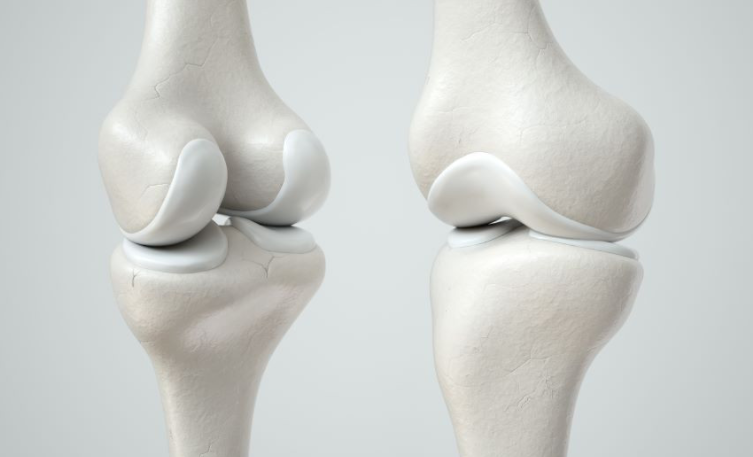

연골은 움직일 때 관절과뼈를 보호하는 쿠션입니다. 그러나 나이가 드신 분들이나 골관절염 환자의 경우에는 연골이 시간이 지남에 따라 마모되어 통증과 불편함을 유발할 수 있습니다.

골관절염은 노년기와 관련이 없는 경우가 많지만 연골은 모든 사람이 다양한 속도로 퇴화됩니다. 따라서 연령이나 상태에 관계없이 연골을 보호, 유지, 보충 및 복구할 수 있는 영양가 있는 음식을 섭취하는 것은 권장합니다.